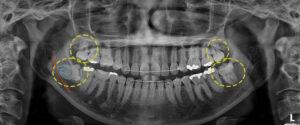

먼저 첫 번째 소개해 드릴 환자분은

다행히 하악 우측에만 사랑니를

가지고 계셨는데요.

잇몸 안쪽이 간헐적으로 부어서

본 원에 내원해 주셨어요.

육안으로 보기에도 잇몸이 부어있던 상태라

정확한 판단을 위해 파노라마와

CT 촬영을 해보았어요.

환자분의 경우 수평 매복 되어 발치 난이도는

높았지만 다행히 신경관과 맞물려 있는

상태는 아니였어요.

발치를 위해 잇몸 절개를 한 후

치아를 쪼개서 발치를 진행하였으며,

잔존 치근이나 부작용 없이 깔끔하게 발치된

모습을 보실 수 있어요.👏